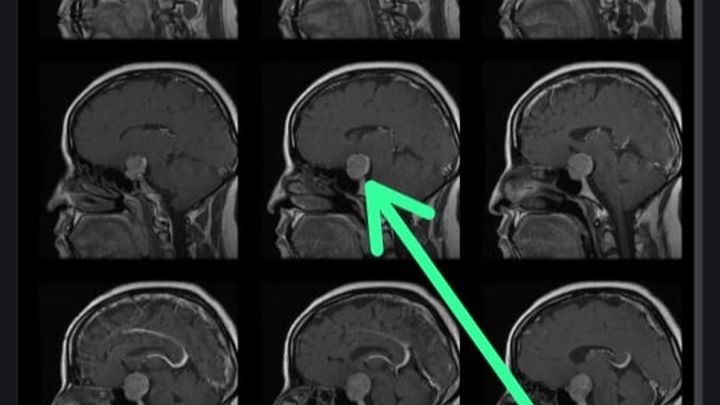

Recientemente, me diagnosticaron un tumor cerebral (macroadenoma en la hipófisis), se ha determinado que necesito una operación urgente para tratar esta condición. Esta noticia ha sido un desafío enorme para mí y mi familia, pero estamos determinados a enfrentarla con valentía y optimismo.